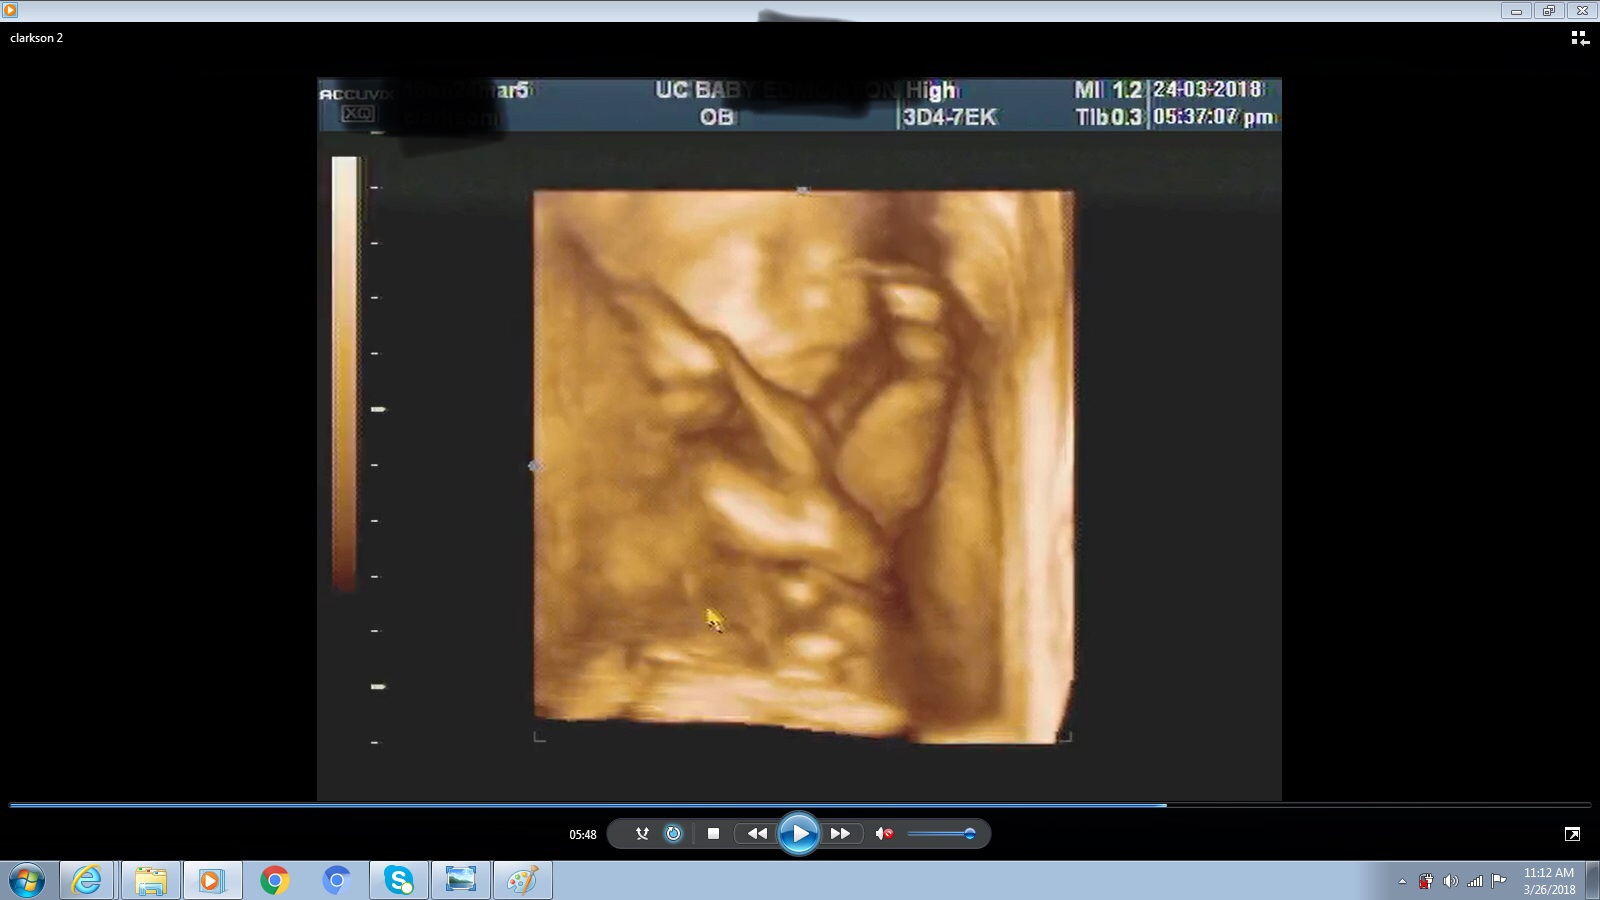

I only have one more picture, finally got it to upload. This was taken at the same time as the first one.

No obvious gender clues from your newest pic but it does make me more inclined to think that it is the leg in the first pic and not the nub.